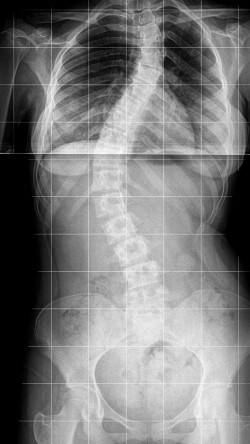

Pasak kineziterapeutės G. Damušytės, skoliozė – tai patologija, kuri pasireiškia stuburo iškrypimu į šoną. „Žiūrint į žmogų iš nugaros sveikas stuburas atrodo kaip tiesi linija. Skoliozės atveju stuburas ima krypti į šoną. Iškrypimai gali vystytis tiek krūtininėje, tiek juosmeninėje stuburo dalyje. Deformacija konstatuojama tada, kai stuburo pakrypimo laipsnis pagal vertinimo skalę pasiekia 10 laipsnių ir daugiau. Ligai progresuojant pakinta laikysena, atsiranda ryški asimetrija“, – sako specialistė.

G. Damušytė pasakoja, kad skoliozė gali būti įgimta, atsirasti dėl sutrikusio raumenų tonuso, dėl įvairių genetinių ligų ir sindromų. Vis dėlto net 80 proc. diagnozuojamų atvejų – idiopatiniai,

t. y. tokie, kurių priežastis taip ir lieka nenustatyta. „Dažniausiai ši patologija diagnozuojama paauglystėje, tarp 10 ir 17 metų, kai jaunas organizmas auga bene sparčiausiai per visą gyvenimą“, – sako kineziterapeutė.

Negydoma skoliozė gali vystytis į stiprią stuburo deformaciją, kuri riboja gyvybinį plaučių tūrį, funkcinius judesius, mažina fizinį pajėgumą ir daro įtaką kitiems su gyvenimo kokybe susijusiems veiksniams.